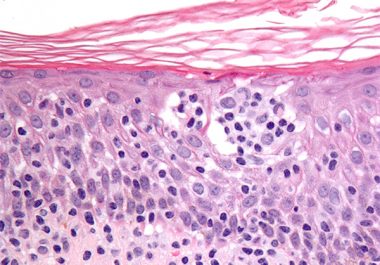

The FDA has approved a new immunotherapeutic for treating two types of cutaneous T-cell lymphoma, mycosis fungoides and Sézary...